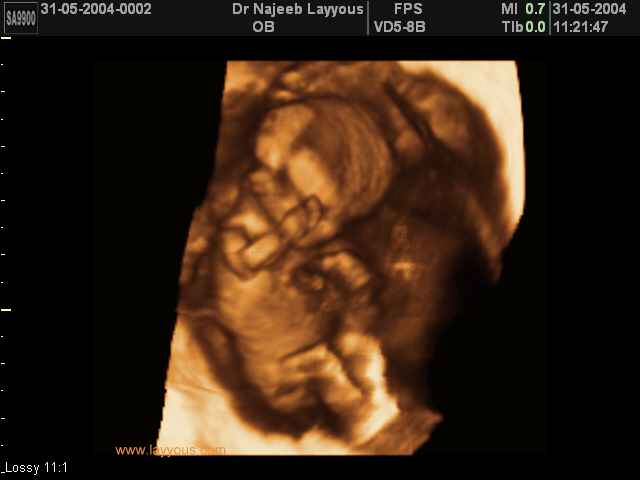

- First Trimester Ultrasound Photos

3D First Trimester Ultrasound Scan Photos ( Early Pregnancy Ultrasound Photos ) | Dr N Layyous